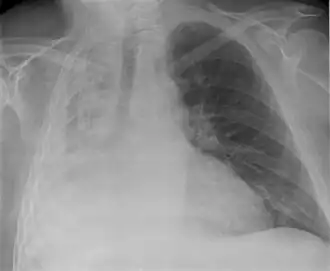

| Raio X de atelectasia do pulmão direito. | |

O colapso pode ser detectado por[2]:

- Raio X torácico;